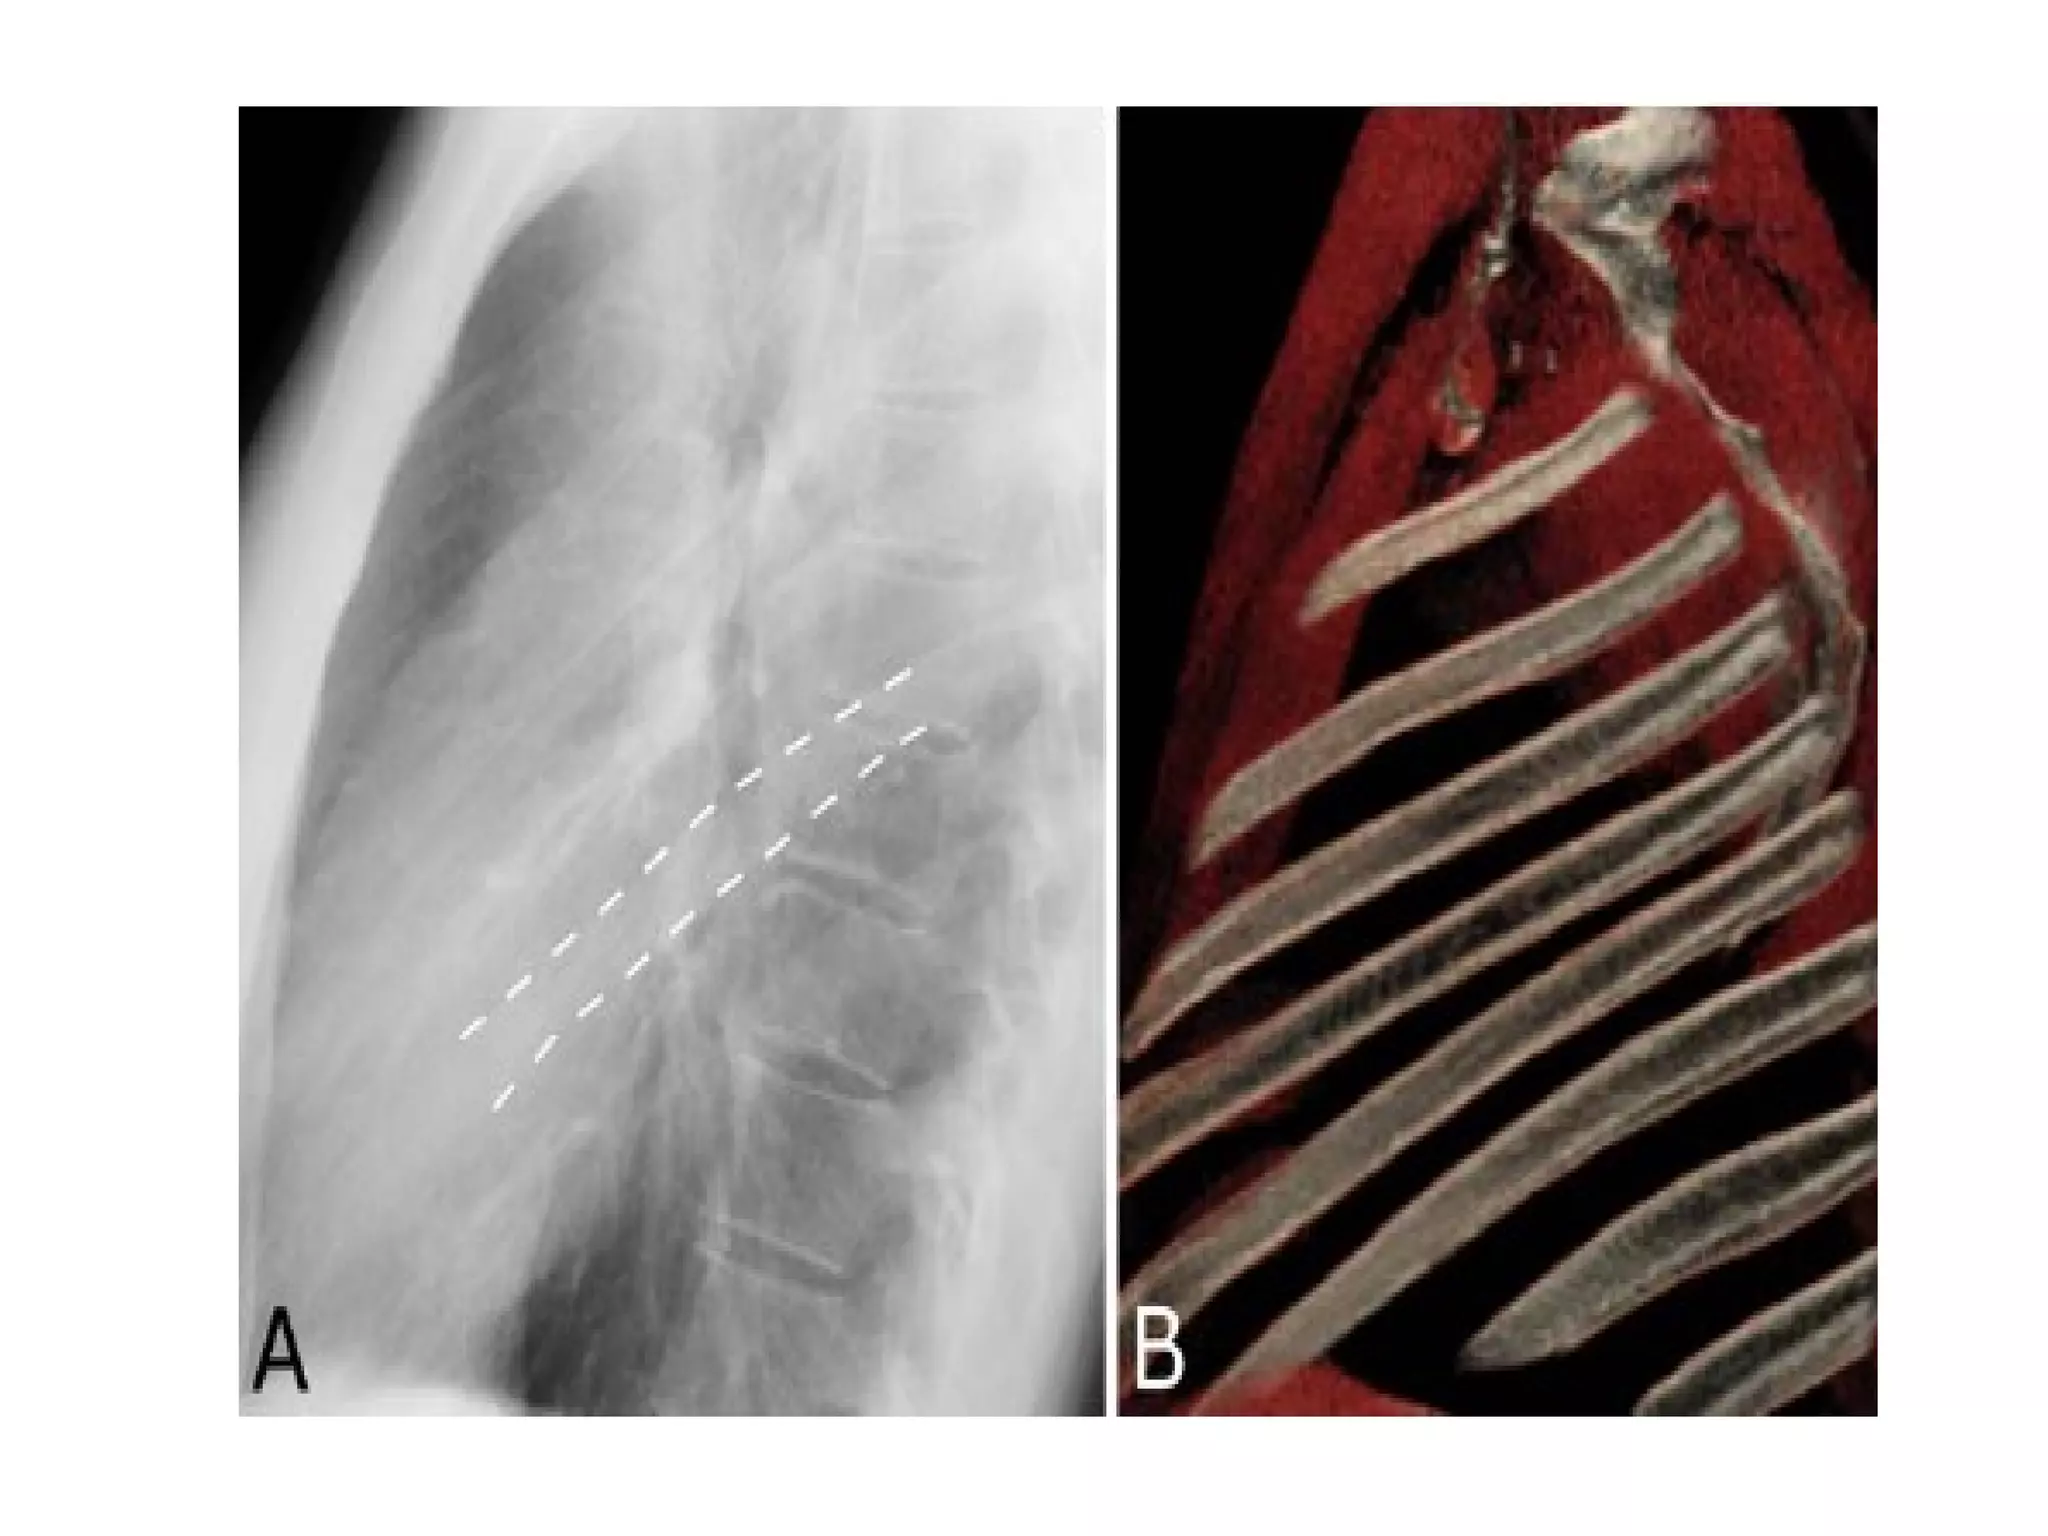

The fissures

The main fissures

The horizontal fissure is seen often incompletely

on PA film

The oblique fissures are seen on lateral film

commence posteriorly at the level of T4 or T5

passing through the hilum. The left is steeper

and finishes 5cm behind the anterior

costophrenic angle, where as the right ends just

behind the angle.

Accessory fissures, the azygos fissure is

comma shaped and nearly always right sided.

The fissures The mainfissures The horizontal fissure is seen often incompletely on PA film The oblique fissures are seen on lateral film commence posteriorly at the level of T4 or T5 passing through the hilum. The left is steeper and finishes 5cm behind the anterior costophrenic angle, where as the right ends just behind the angle. Accessory fissures, the azygos fissure is comma shaped and nearly always right sided.